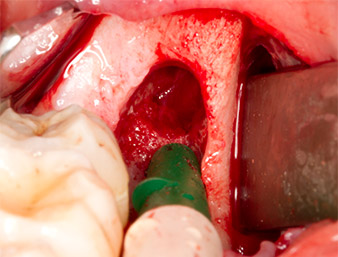

To obtain autogenous material for subsequent wound treatment, healthy bone chips were harvested from the surroundings of the root remnant with a piezo surgical instrument (Piezomed B5) (Fig. 5).

Piezomed B5

Fig. 5: Bone in the region of the alveole is lifted with a chisel-shaped piezo surgical instrument (Piezomed B5). This bone is used as autologous augmentation material after removal of the root remnant (cf. Fig. 13 and 14).

The autogenous tissue was removed with the scraper-shaped section of the working part of the instrument and stored in a physiological saline solution until further use (cf. Fig. 13).

To expose the root remnant with as little trauma as possible to the tissue, a further instrument was used (Piezomed S2) that is primarily indicated for preparing the lateral window in augmentations of the sinus floor. The diamond-coated ball was additionally used to smooth sharp bone edges (Fig. 6 and 7). All the Piezomed attachments were used with the relevant automatic default setting without booster function.

Piezomed S2

Fig. 6: The root remnant is carefully exposed with a diamond-coated spherical instrument (Piezomed S2), bone edges are smoothed.